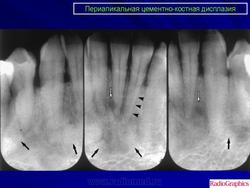

Стоматология. Дисплазия цементо - костная. +

Дисплазия цементо - костная.